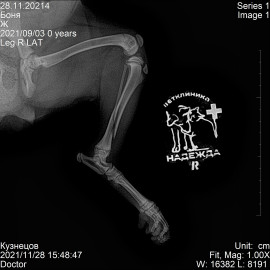

Обратились в нашу клинику с жалобами на то, что собака не встает на правую заднюю лапу. Ребенок играл с собакой, после чего собака перестала вставать на лапу. После осмотра и рентгена был поставлен диагноз - перелом правой голени. Проведена операция - остеосинтез правой голени.

Снимок 2-3 после операции.